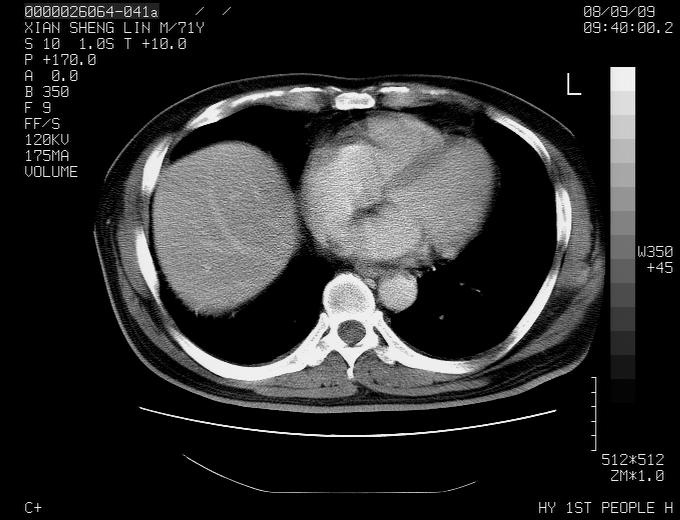

标题: CT15869:男性,71岁,因咳嗽而就诊,请讨论右上肺病变性质 [打印本页]

标题: CT15869:男性,71岁,因咳嗽而就诊,请讨论右上肺病变性质

患者,男性,71岁,因咳嗽而就诊,

1,右肺中心型ca,气管隆突旁淋巴结转移。

2,右膈明显抬高,建议肝脏扫描排除转移或原发灶。